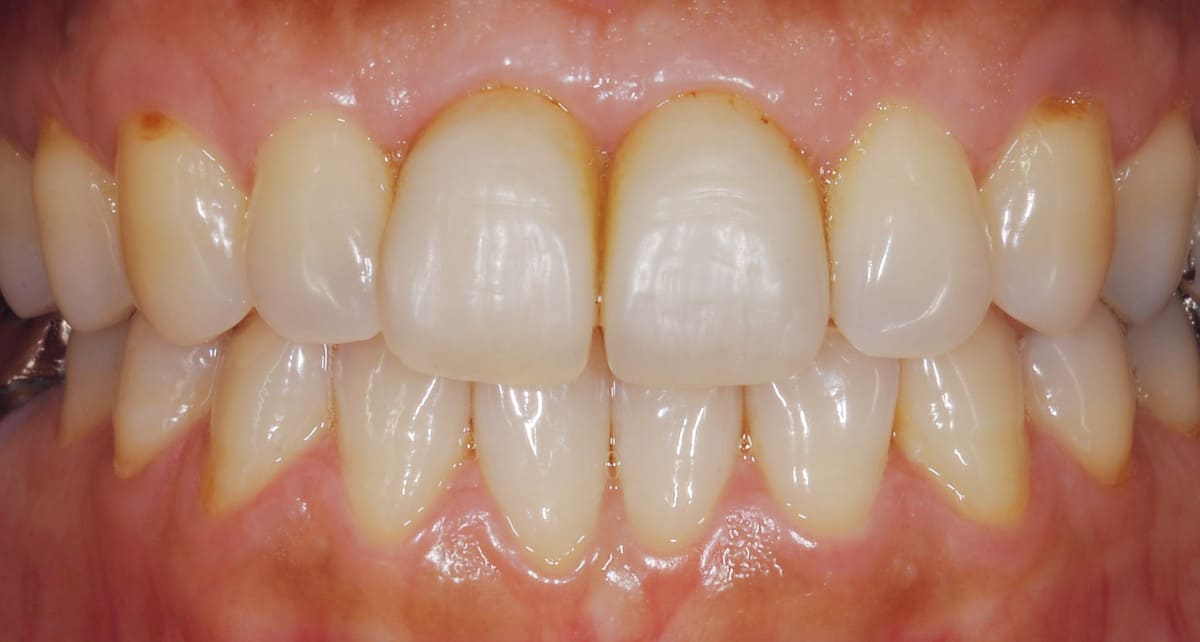

ジルコニア|ダイヤモンド並みに硬くカラダへの馴染みがいい。

Before

After

セラミックの一種のジルコニアで作った被せ物(クラウン)を使った治療。ジルコニアは人工ダイヤモンドと呼ばれるほどの硬度があるので奥歯にも適していてカラダには馴染みがいい素材。ただし透明感はセラミックより出しにくい。

【料金】10万円〜

【治療期間】1週間〜3週間程度

(特別な機材がある病院ではワンデイ治療が可能)